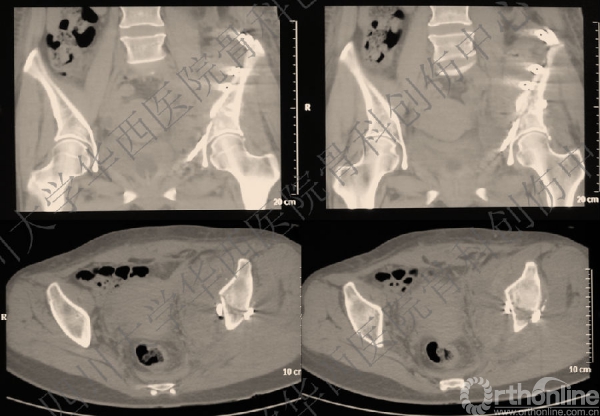

术前CT

入院后行左股骨髁上牵引,积极术前准备,做CT,证实双柱骨折的诊断。